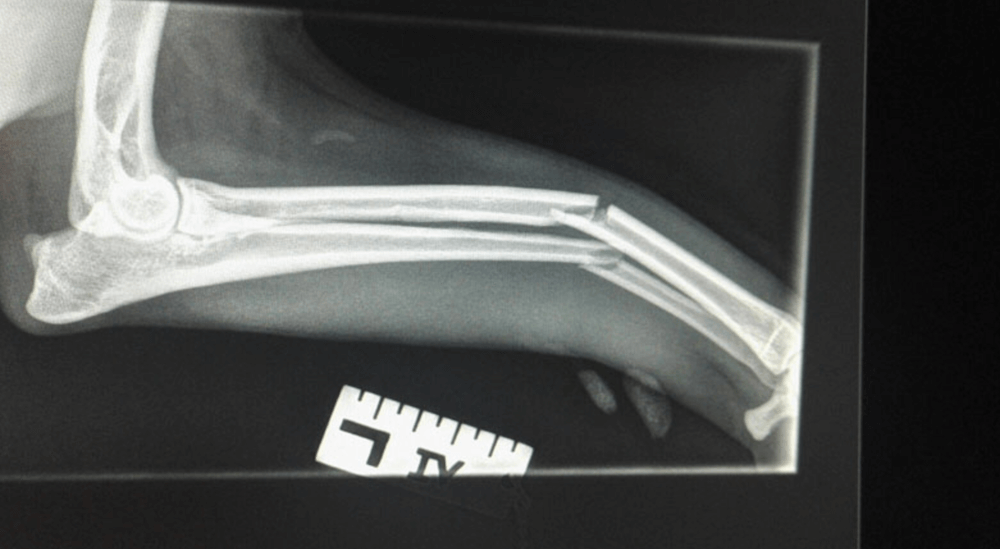

Tibia Fracture Repair